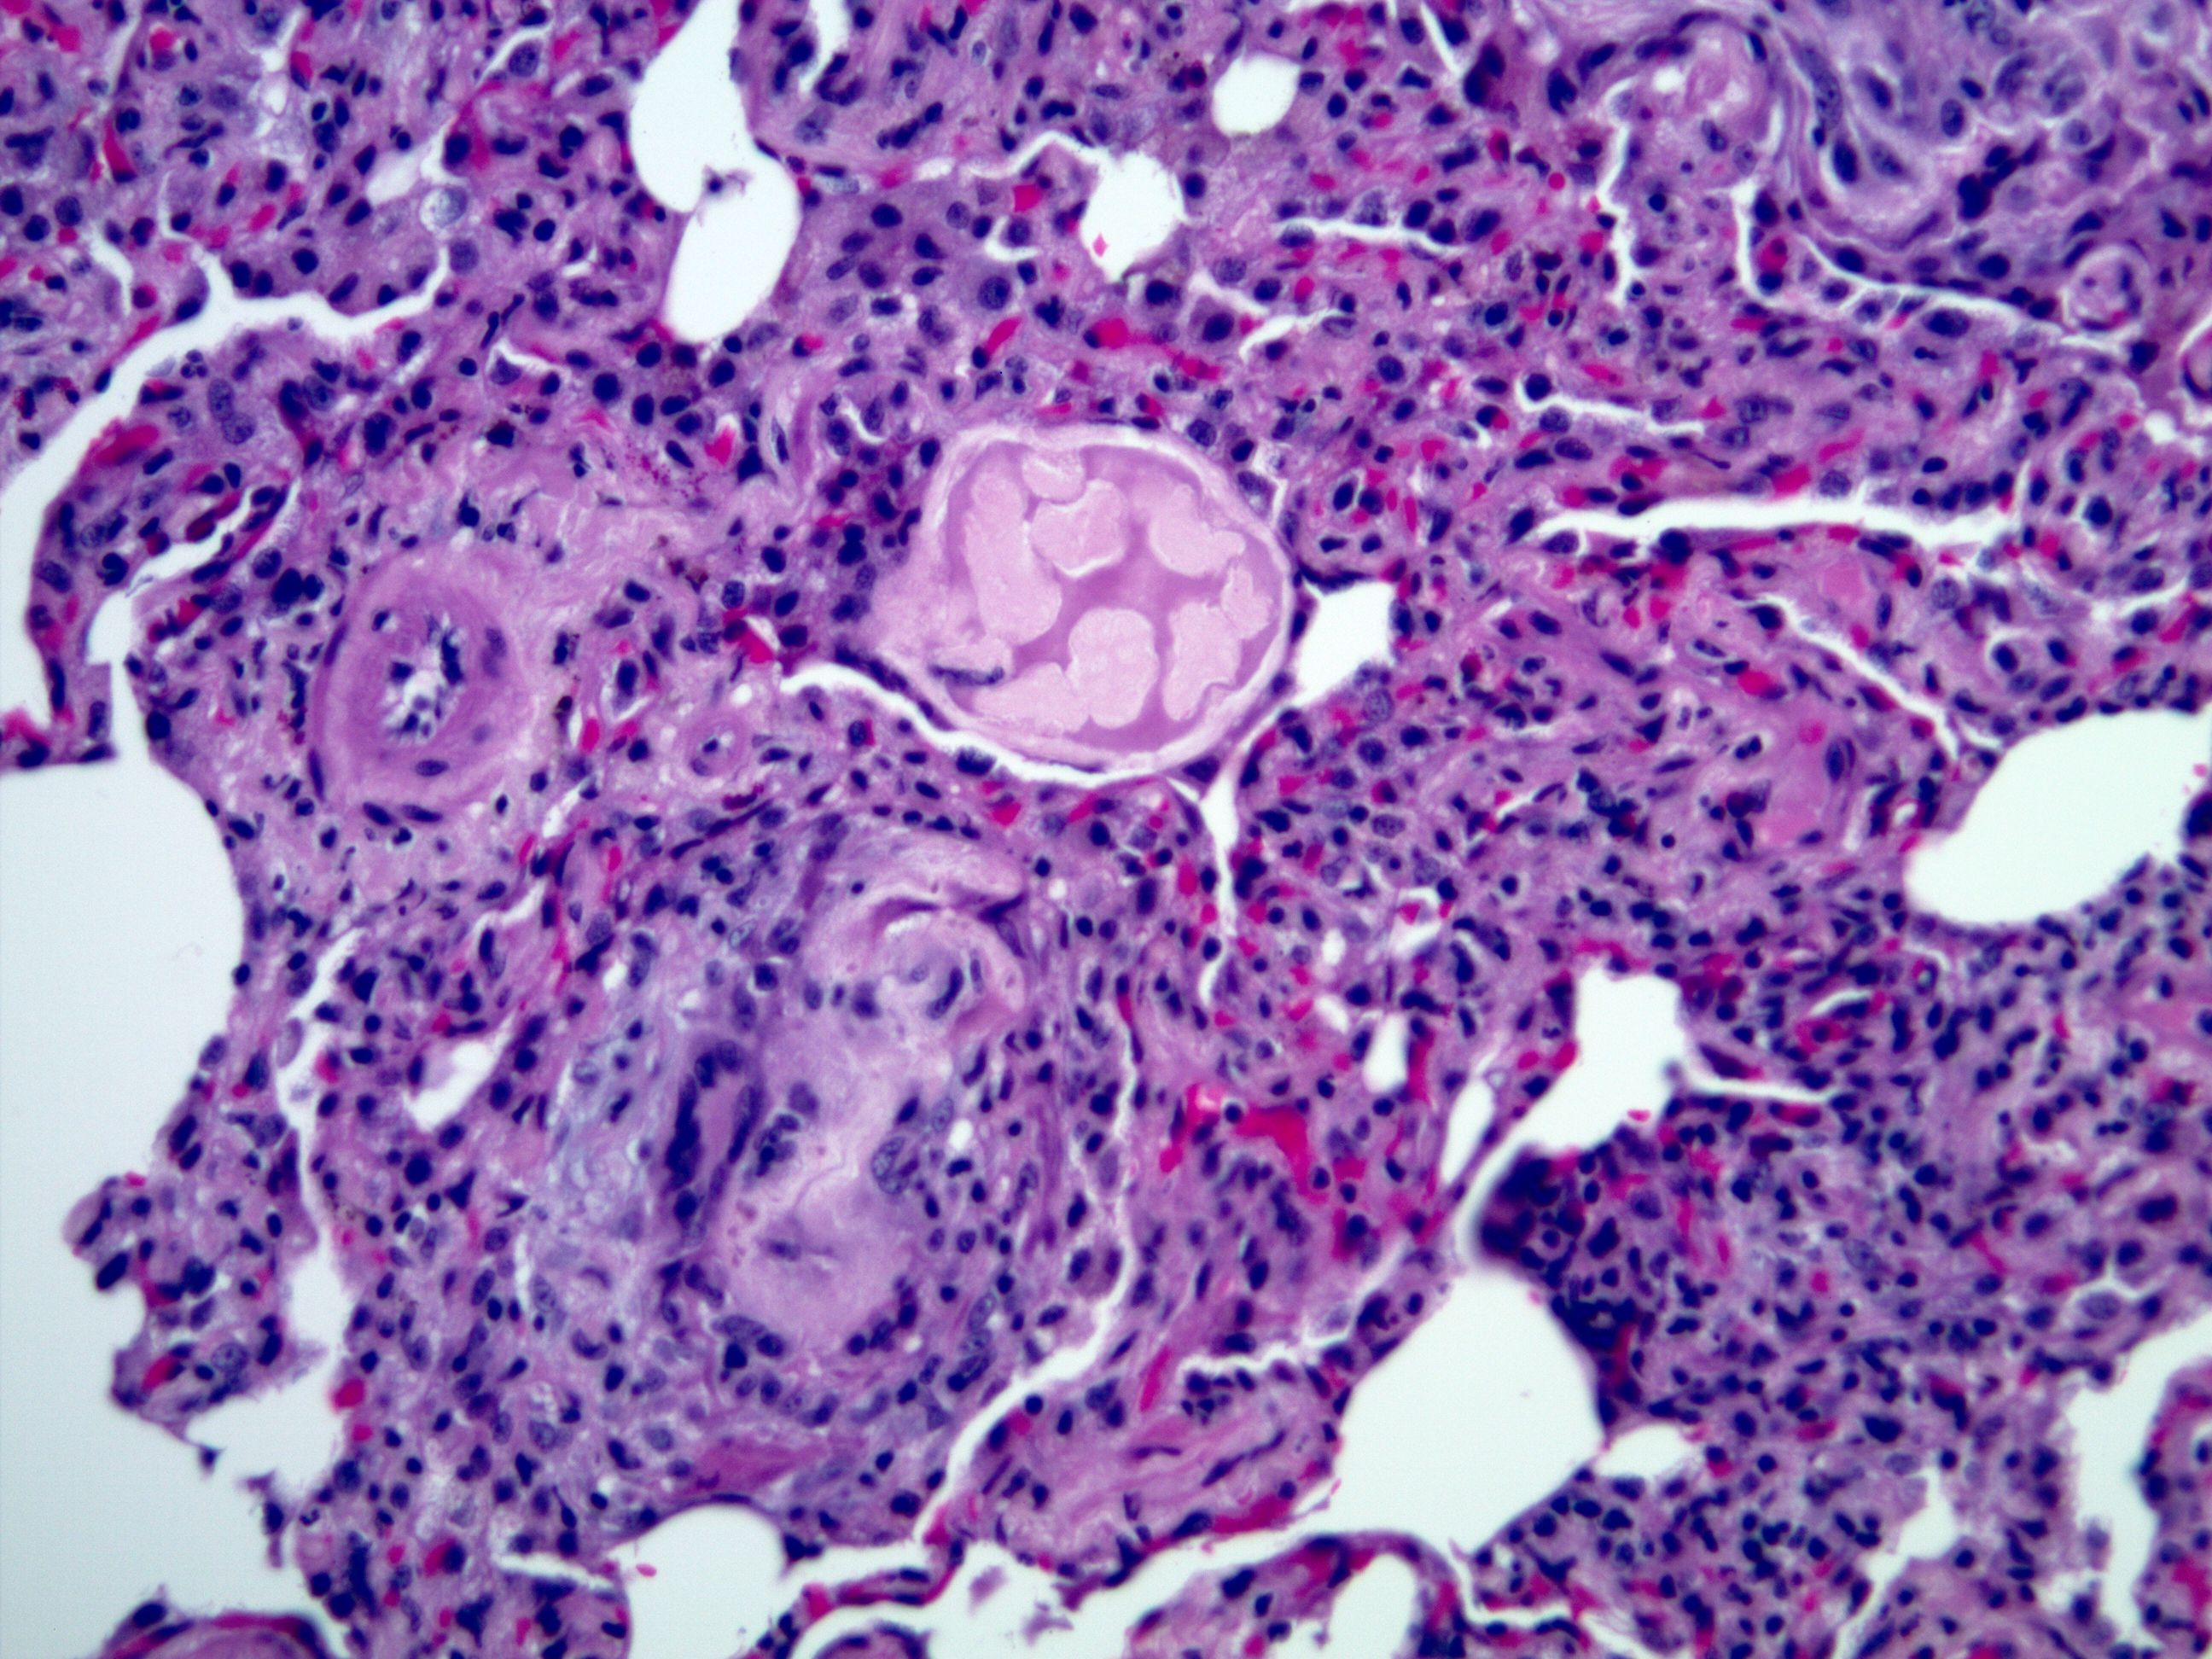

Lung histology. Aspirated food constituents corresponding to meat Aspirated Food Into Lungs — usually, it’s food, saliva, or stomach contents that make their way into your lungs when you swallow, vomit, or experience heartburn. — aspiration pneumonia is a type of pneumonia caused by the accidental infiltration of food or other substances. You can also aspirate food that travels. This can be whilst attempting to swallow or. Germs, food particles,. Aspirated Food Into Lungs.